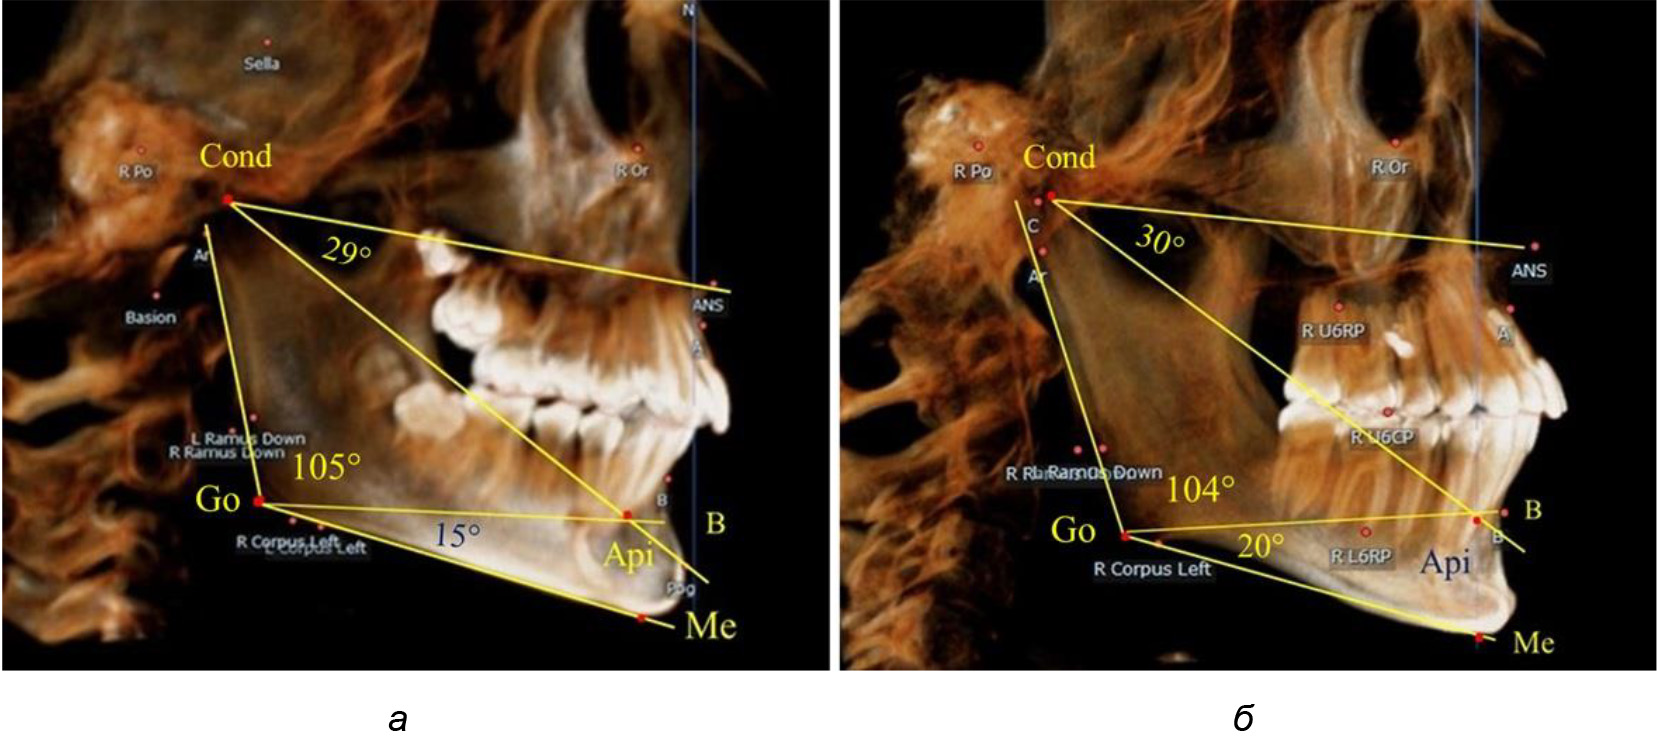

Таким образом, в периоде молочного прикуса с оптимальными окклюзионными соотношениями, несмотря на линейные размеры в вертикальном и сагиттальном направлении, которые, безусловно, меньше параметров взрослых людей, величина основного угла гнатической части лица SNA-Cond-Api соответствовала параметрам людей с полностью сформированным физиологическим прикусом постоянных зубов. Анализируя данные рентгенограмм детей в периоде сменного прикуса, отмечено, что величина основного угла гнатической части лица SNA-Cond-Api, так же как в молочном и постоянном прикусе, в норме составляла от 28 до 32°. В то же время угол нижней челюсти и его составляющие отличались вариабельностью параметров при различных показателях нижнечелюстного угла. Достоверных различий угла гнатической части после смены нижних медиальных резцов и прорезывания первых постоянных моляров (4 ребенка) не было; происходил очередной этап подъема высоты прикуса и увеличение линейных размеров костей гнатической части, однако угловые параметры были относительно стабильны. После смены всех резцов и замены первых молочных моляров первыми премолярами (6 человек) увеличивались линейные размеры при сохранившихся угловых показателях гнатической части лица (рис. 5).

Рис. 5. Варианты ТРГ после прорезывания ППМ и нижних резцов (а), всех резцов и первых премоляров (б)

Таким образом, в период сменного прикуса с оптимальными окклюзионными соотношениями, несмотря на увеличение линейных размеров в вертикальном и сагиттальном направлении, по сравнению с прикусом молочных зубов, величина основного угла гнатической части лица SNA-Cond-Api соответствовала показателям как постоянного, так и молочного прикуса с физиологическими окклюзионными соотношениями.

После смены всех молочных зубов (анализ 9 ТРГ) и после прорезывания вторых постоянных моляров (7 человек) происходил очередной этап подъема высоты прикуса с увеличением размеров костей гнатической части лица. Однако величина основного угла гнатической части лица SNA-Cond-Api, так же как в молочном и сменном прикусе, в норме составляла (30,02 ± 1,25)°, что не имело достоверных различий (р ˃ 0,05) с аналогичным параметром, анализируемом в других группах исследования. Угол нижней челюсти и его составляющие отличались вариабельностью параметров при различных показателях нижнечелюстного угла (рис. 6).

Рис. 6. Варианты 3D рентгенограмм детей после смены всех молочных зубов (а) и после прорезывания вторых моляров (б)